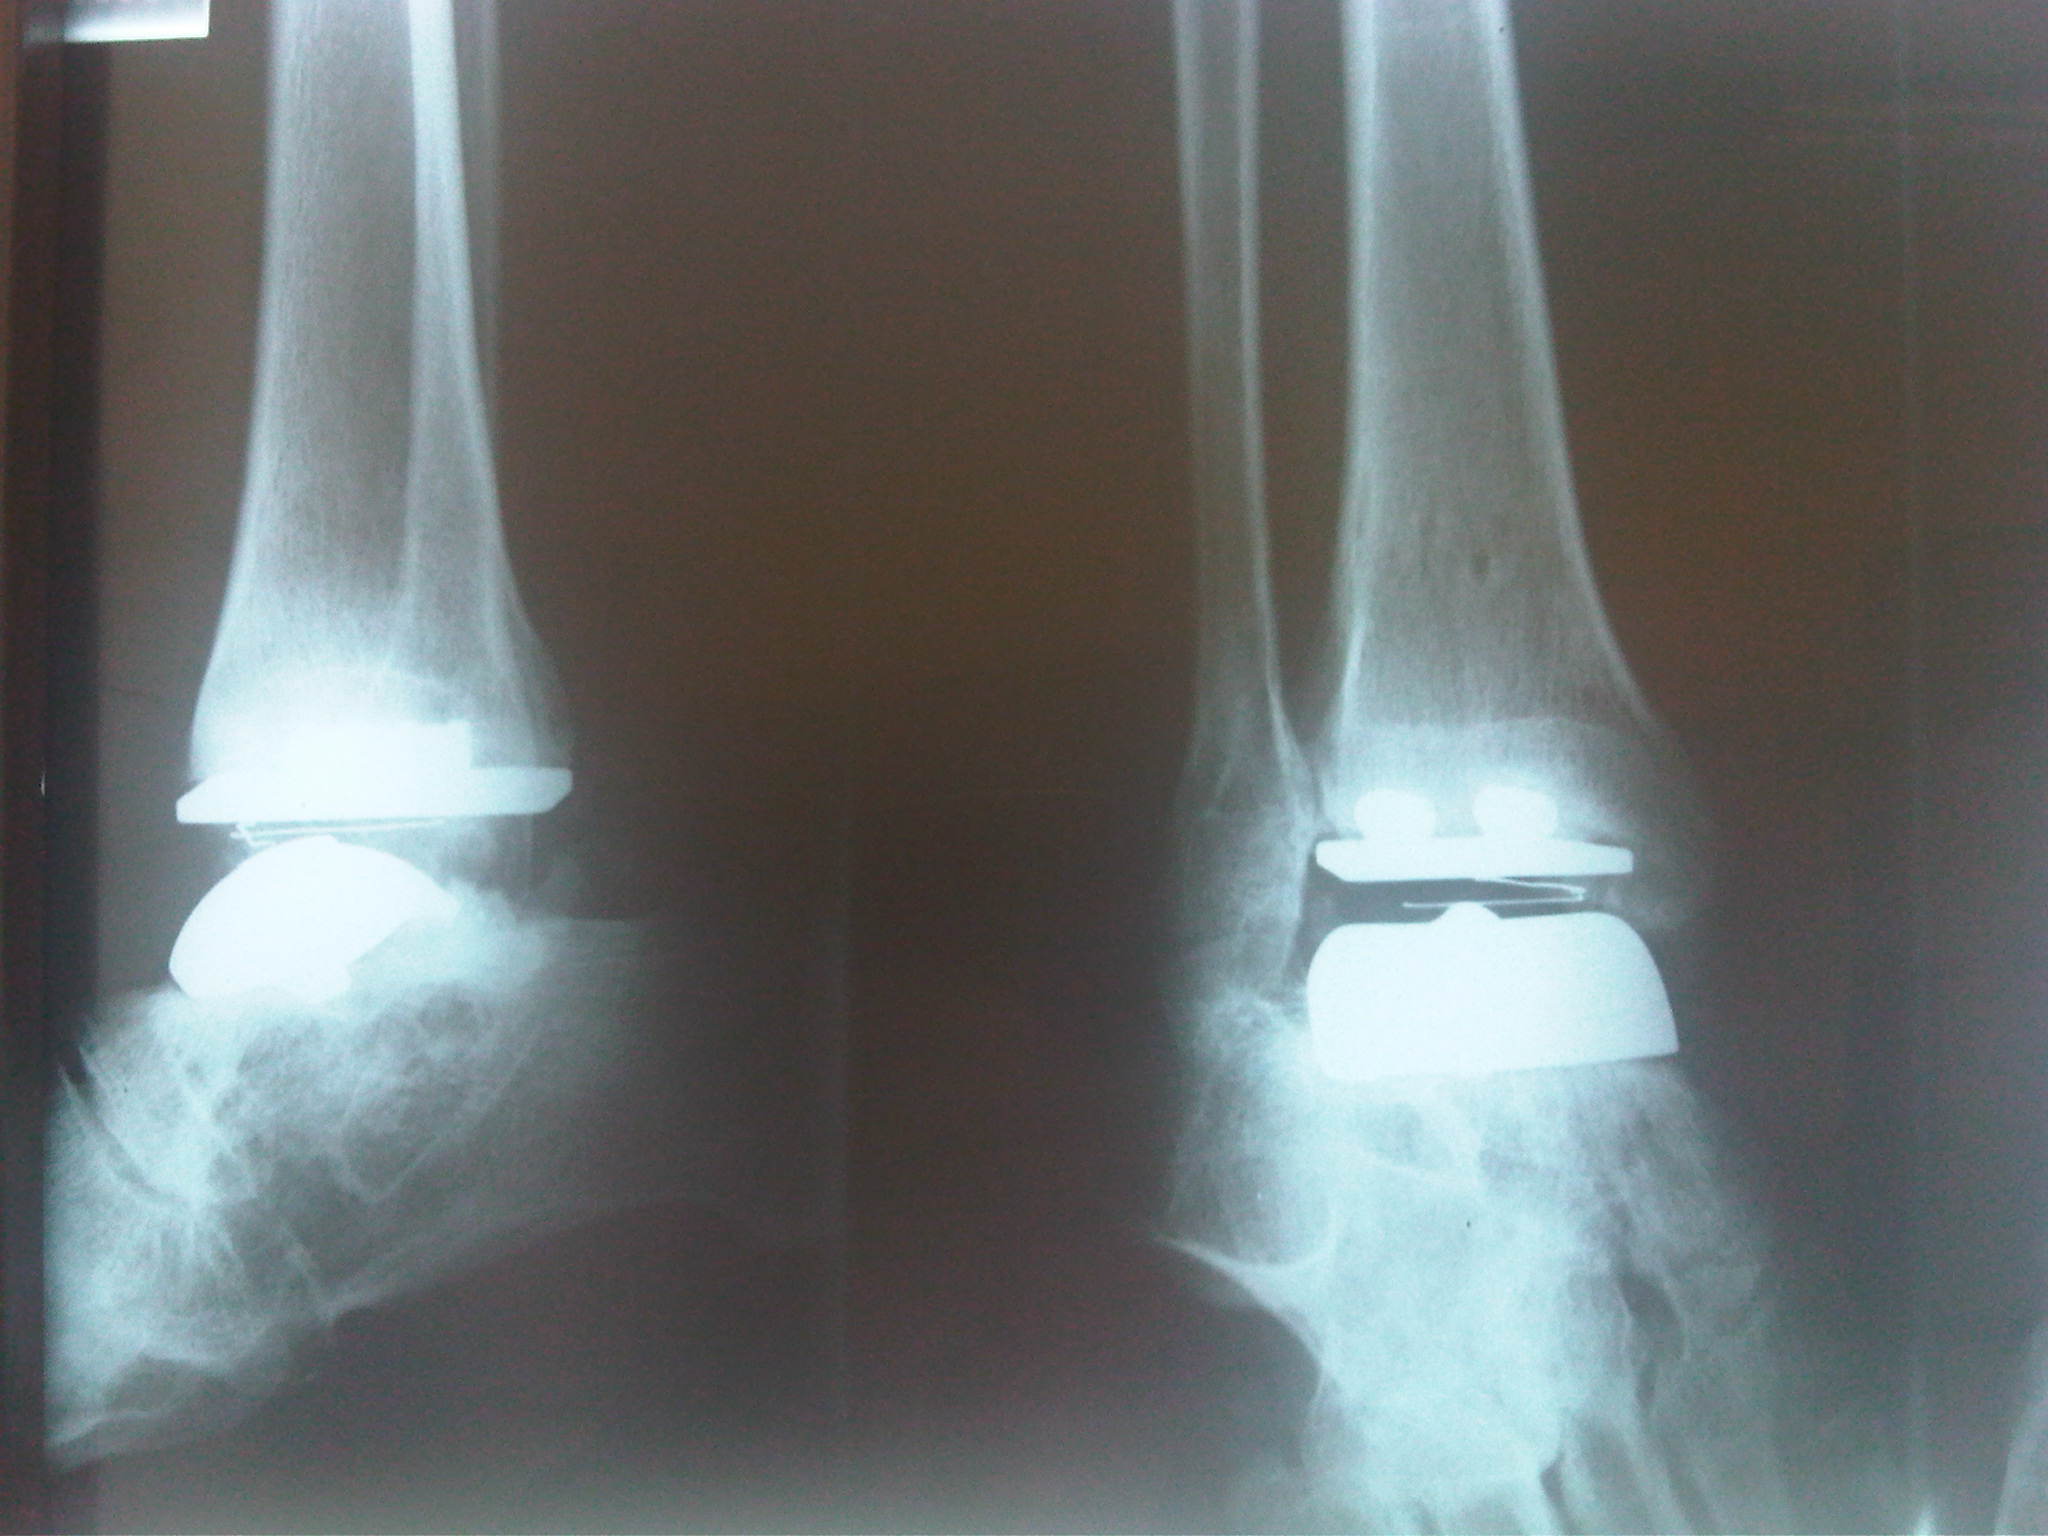

Dificultades peri-operatorias de las artroplastias de tobillo.

Herrera JM, Vasquez D. Moreno D. Rev Col Or Tra. 2010;24(3):158-167.

Artroplastia de Tobillo: Estado del Arte. Parte II.

Herrera JM. Rev Col Or Tra. 2009;23(1):53-61.

Artroplastia de Tobillo: Estado del Arte. Parte I.

Herrera JM. Rev Col Or Tra. 2008;22(4): 247-260.